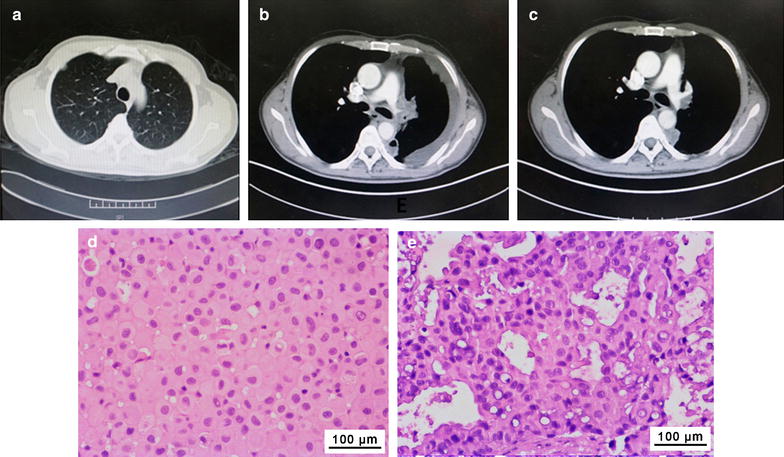

CTC15063EGFR L858R, T790M tumor cells were obtained from a 52-year-old male NSCLC patient (patient CTC15063EGFR L858R, T790M), who had previously presented with stage IV lung cancer with pleura, peritoneum, and right lung metastases. The patient underwent surgical tumor resection and adjuvant chemotherapy with navelbine plus cisplatin. At a follow-up visit approximately 4.5 years later, disease recurrence with right pleura metastasis was found (Fig. 3a). A tumor biopsy specimen tested positive for the EGFR L858R mutation, so the patient was treated with erlotinib. A partial response was achieved, but disease progression with malignant pleural effusion occurred 26 months after beginning erlotinib (Fig. 3b). Pleural fluid was then collected, and malignant cells isolated from the pleural fluid were used to generate the CTC15063EGFR L858R, T790M xenografts. Subsequently, another biopsy sample of the tumor tested positive for EGFR L858R and T790M mutations, so the patient was treated with osimertinib, and his disease was stabilized for 13 months (Fig. 3c). Histological characteristics of the CTC15063EGFR L858R, T790M tumor xenografts were highly similar to the tumor biopsy (Fig. 3d, e).

Fig. 3.

Computed tomography (CT) scans and pathology for patient CTC15063EGFR L858R, T790M and the patient-derived xenograft tumors. CT chest scans of patient CTC15063EGFR L858R, T790M were recorded 4.5 years after undergoing surgical resection and subsequent adjuvant chemotherapy (navelbine plus cisplatin). a Disease recurrence was found in a CT scan as a right sub-pleural nodule on 2012-3-12; b disease progression 26 months after erlotinib treatment was visible in a CT scan as malignant pleural effusion on 2014-6-27; c CT reexamination after 2 months of osimertinib treatment showed stable disease on 2015-10-8. Pathology (H&E staining) of tumor biopsy from d patient CTC15063EGFR L858R, T790M and e a xenograft CTC15063EGFR L858R, T790M tumor after osimertinib treatment